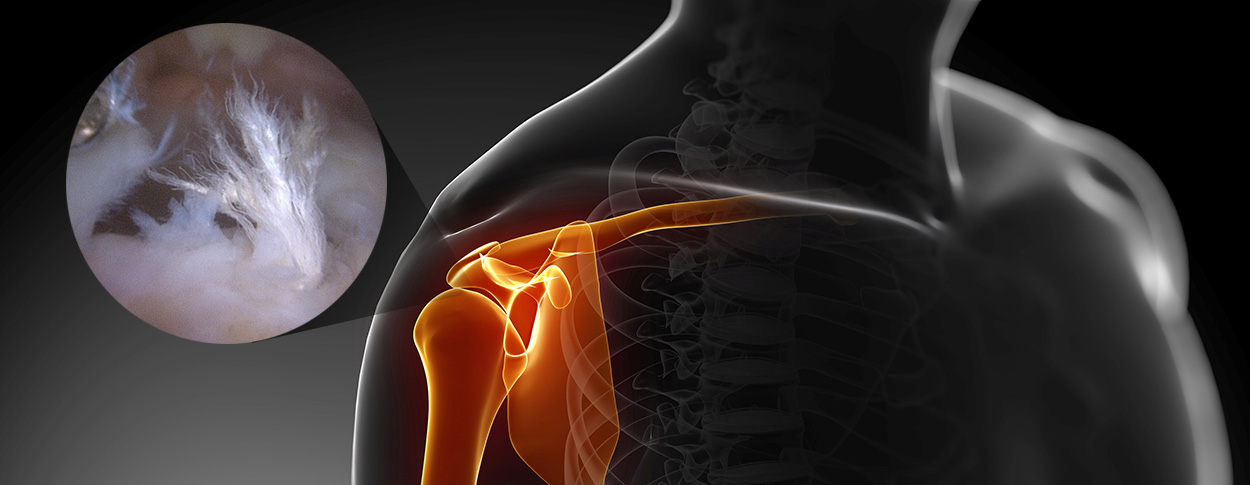

관절내시경은 작은 절개 부위로 고해상도 카메라를 삽입하여 관절 내부를 관찰하는 방법으로

화면을 통해 병변 부위를 직접 확인하면서 손상 정도에 따라 파열된 힘줄을 봉합하거나 염증을 제거할 수 있습니다.

손상된 조직을 봉합 혹은 제거하기 위해선 작은 수술 도구가 필요하며, 이들 도구는 작은 추가 절개구로 삽입되어 사용됩니다.